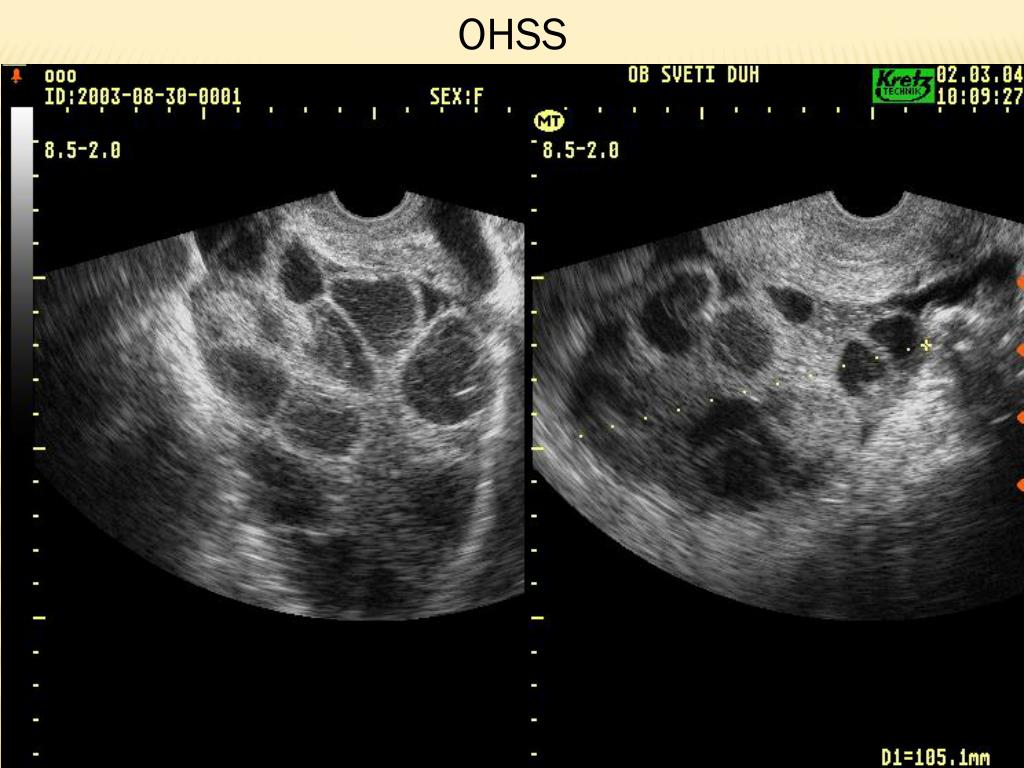

18. OHSS

19. 5 hiperstimulacija koje su zahtjevale prijem u JIL Od 2011. bez teškog oblika OHSS Zakon – ciljano manji broj oocita; blaži protokoli Antagonistički protokol s agonistom umjesto HCG-a!!! OHSS (2003-2013) SV Duh